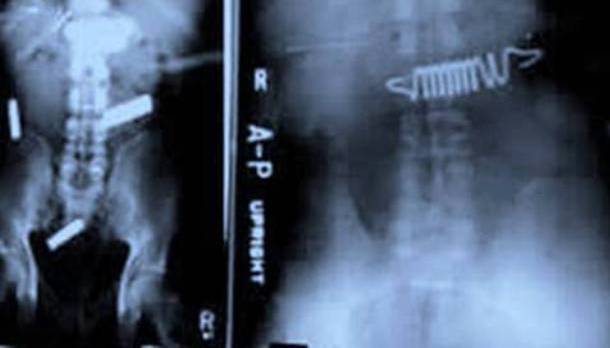

19. More Smuggling...

This X-ray shows more smuggling which occurred in two prisoners in Raleigh, North Carolina. These two were found trying to smuggle batteries and bed springs inside. But, they were found inside their stomachs. As we all know...swallowing batteries is NOT a good idea.Advertisement